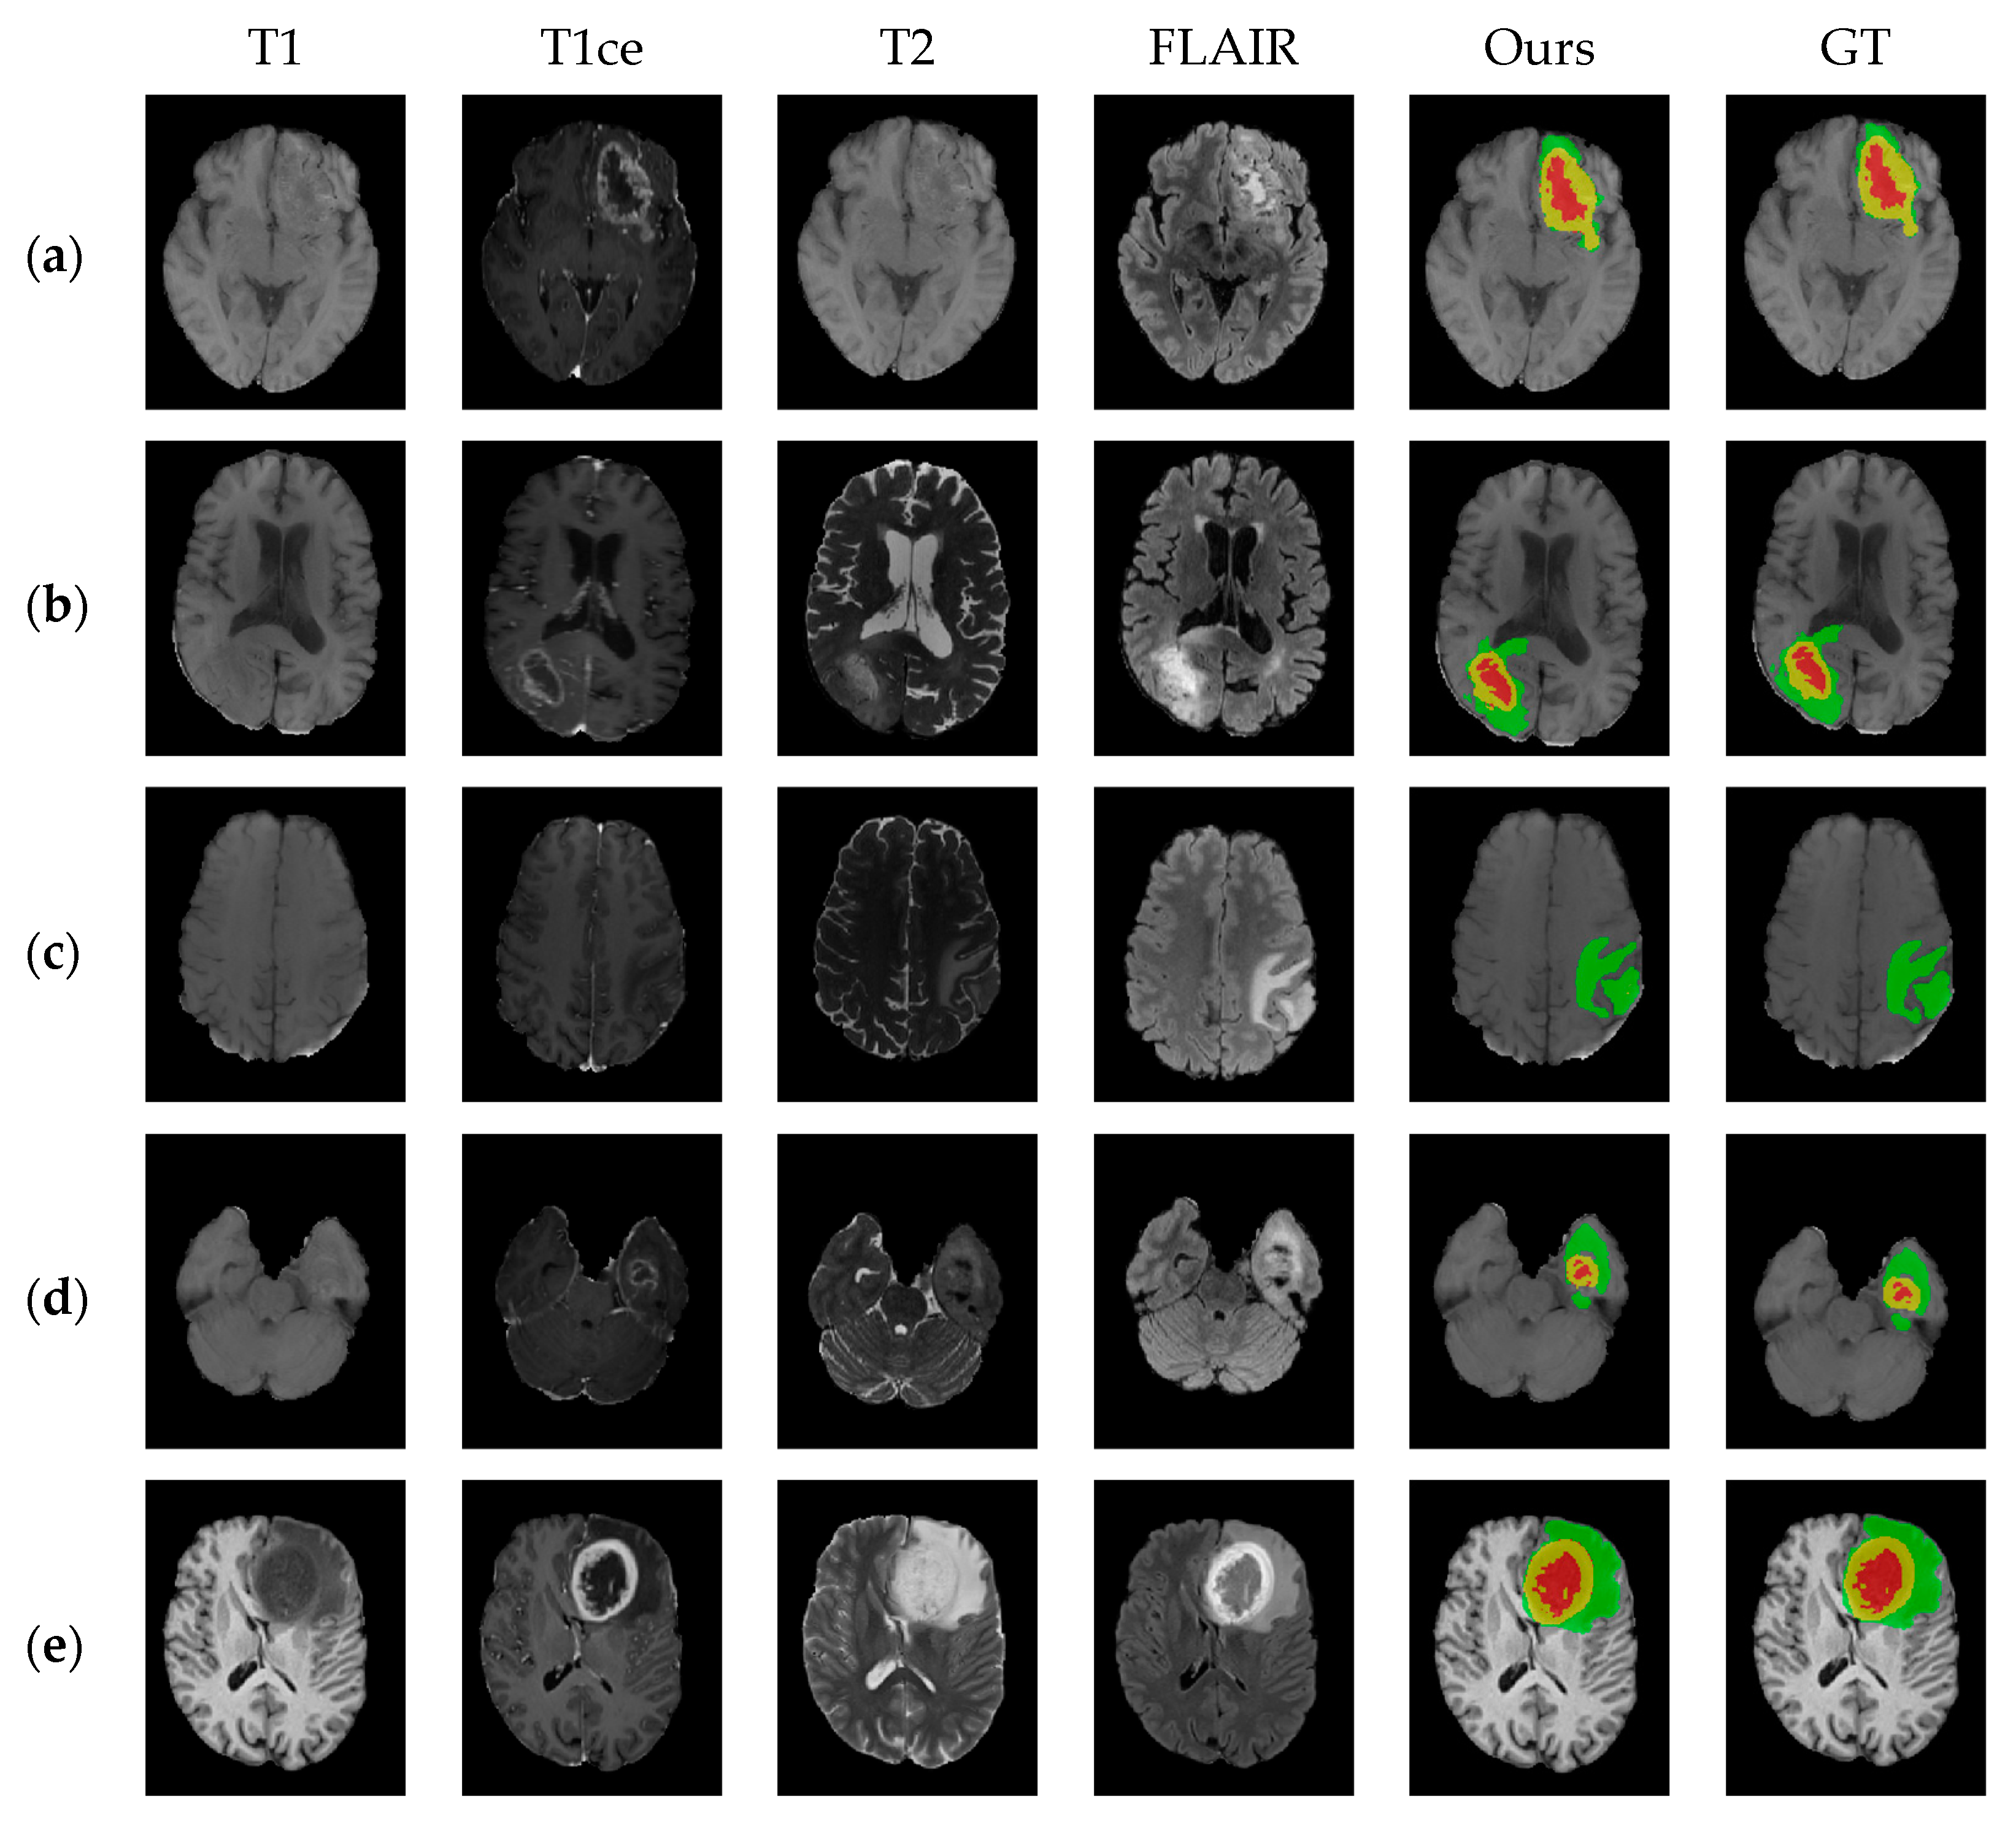

5. Results

5.1. Comparison with Other Methods